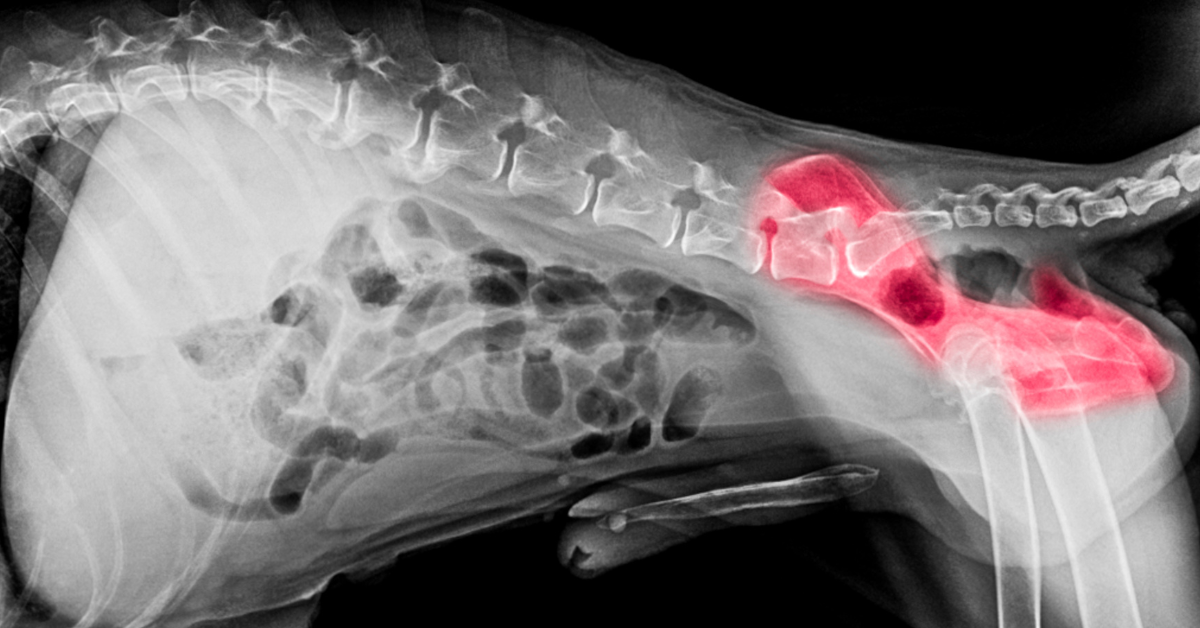

To explain it in simpler terms, the vet will manually exert pressure on the hind legs or by using a device to examine your dog’s mobility and level of discomfort. He will conduct further examinations to look for any grinding noise from the joints. To confirm the diagnosis of hip dysplasia, the vet may ask for an x-ray to be done.

Similar to hip dysplasia, a radiograph will also confirm the hip dislocation. Besides confirming the dislocation, the x-ray will also help determine if a part of the hip has been fractured.

If your dog has had lameness for over two weeks, radiographs will be conducted on the affected joint to understand the cause.

Many owners report irritability in their pets due to joint pain. Like the other conditions mentioned above, a radiograph is needed for this one, too, to confirm the diagnosis. The femoral head’s misshapen appearance will be visible through the radiograph.